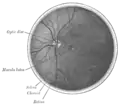

Pared posterior del ojo izquierdo porción posterior.

Partes del ojo identificadas en la página de la imagen.